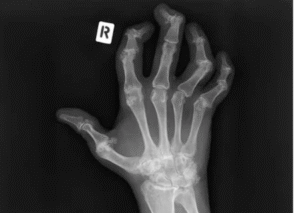

Temuan Sinar-X pada Psoriasis Arthritis

Beberapa perubahan khas yang dapat terlihat melalui sinar-X meliputi:

- Perubahan pada sendi-sendi ujung jari tangan dan kaki

- Keterlibatan sendi yang asimetris, terutama pada sendi sakroiliaka

- Erosi: kerusakan pada tulang dan tulang rawan yang berdekatan dengan ruang sendi

- Deformitas “pensil dalam cangkir”: akibat erosi periartikular dan resorpsi tulang, sehingga tulang tampak seperti pensil yang masuk ke dalam cangkir

- Subluksasi: pergeseran posisi sendi dari keselarasan normalnya

- Ankilosis: penyatuan tulang melintasi ruang sendi, yang menyebabkan kekakuan permanen

- Pertumbuhan tulang baru yang tipis dan padat di sekitar sendi, dikenal sebagai “kumis” dan “taji” tulang

- Pengendapan garam kalsium di area perlekatan ligamen dan tendon ke tulang, serta tanda-tanda lain dari entesopati

- Falang gading: peningkatan kepadatan tulang (radiodensitas) pada seluruh falang akibat pembentukan tulang periosteal dan endosteal

Sinar-X pada Psoriasis Arthritis